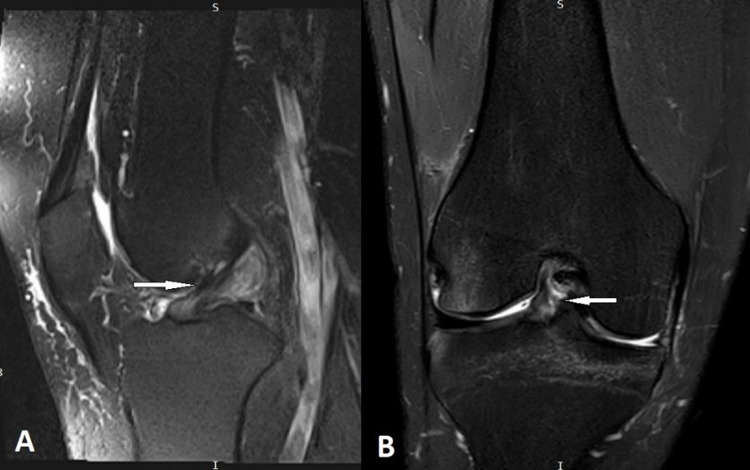

The Anterior Cruciate Ligament (ACL) is considered the most commonly injured ligament of the knee. Magnetic Resonance Imaging (MRI) has become an indispensable imaging tool and modality of choice for assessing and managing knee conditions. This article outlines an effective MRI imaging technique that improves the diagnostic accuracy of ACL injuries of the knee, covering the appropriate pulse sequences and optimal imaging planes. Furthermore, the article provides a comprehensive review of the appearance of complete and partial ACL tears on MRI in the acute and chronic phases. In addition, it identifies and illustrates the primary MRI signs (signs related to the absence or abnormal visualization of the ACL fibers) and secondary MRI signs (signs related to the mechanism of injury or associated knee injuries) of ACL injury.